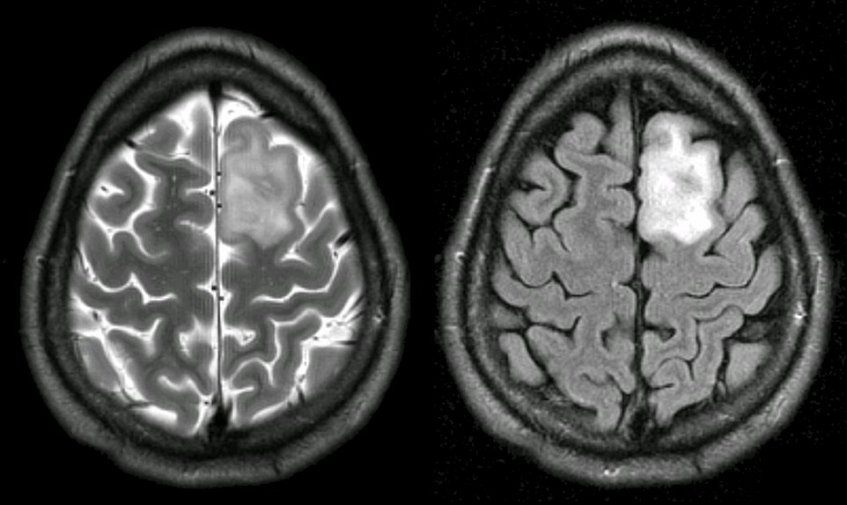

腦膠質(zhì)瘤占顱內(nèi)原發(fā)腫瘤的45%左右,其中惡性膠質(zhì)瘤占多數(shù)。WHO根據(jù)腦膠質(zhì)瘤惡性程度將其分為四級:

其中三級和四級為惡性膠質(zhì)瘤,很容易復(fù)發(fā)。間變性星形細(xì)胞瘤發(fā)病平均年齡較小,約為40歲,膠質(zhì)母細(xì)胞瘤發(fā)病的平均年齡約53歲,男性多于女性,男女之比為1.5:1。

腦膠質(zhì)瘤的病理分級、生長位置、手術(shù)切除程度等都是決定腦膠質(zhì)瘤能否長期生存的重要因素。

惡性腦膠質(zhì)瘤雖然少發(fā)生顱外轉(zhuǎn)移,但容易復(fù)發(fā),因腫瘤呈浸潤性生長,侵襲性較強(qiáng)。20世紀(jì)30年代,Dandy曾報道,即使對腦膠質(zhì)瘤行大腦半球切除,仍出現(xiàn)健側(cè)大腦半球腫瘤復(fù)發(fā),可見其侵襲性之強(qiáng),在一些大腦復(fù)雜部位,手術(shù)很難做到完全切除腫瘤,因此復(fù)發(fā)率較高。

膠質(zhì)母細(xì)胞瘤中位生存期不足兩年,特別是功能區(qū)腦膠質(zhì)瘤較大地限制了手術(shù)切除范圍,復(fù)發(fā)率更高,預(yù)后更差。隨著神經(jīng)電生理監(jiān)測、立體定向定位、術(shù)中核磁共振、功能核磁共振、皮層功能定位、術(shù)中喚醒及PECT輔助手段的應(yīng)用,提高了功能區(qū)膠質(zhì)瘤的手術(shù)質(zhì)量,延長了生存期。目前手術(shù)的原則仍是在順利的前提下較大范圍切除腫瘤,因為手術(shù)切除的程度與預(yù)后較為密切相關(guān)。